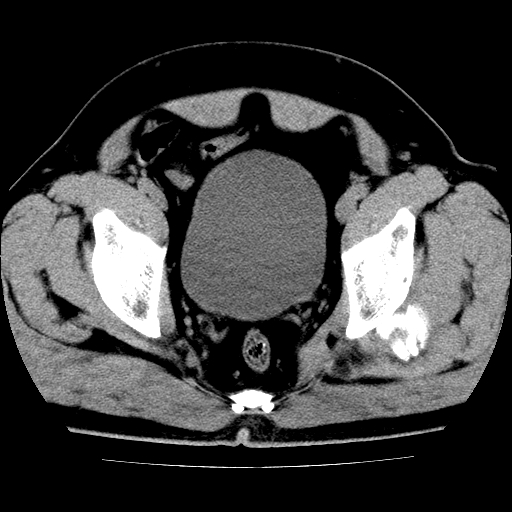

标题: CT21643:男,42岁,车祸伤后左髋关节疼痛剧烈1小时。 [打印本页]

男,42岁,车祸伤后左髋关节疼痛剧烈1小时。

左髋关节脱位并髋臼骨折,左髋关节积血。

左髋关节后脱位并髋臼骨折,左髋关节积血

左髋关节后脱位,大小转子皮质撕脱骨折,关节腔“脂血症”,左侧盆底少量积血,左侧髋臼邻关节囊肿。

左髋关节后脱位并髋臼骨折、股骨头前方骨折,左髋关节积血 。

左髋关节(股骨头)后脱位,并髋臼及股骨头骨折,左髋关节积血。

左髋关节后脱位并髋臼后缘骨折、股骨头前方骨折,左髋关节积血 。我遇到过一例。